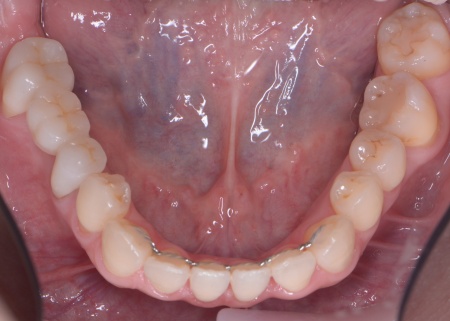

| カウンセリング | 拝見したところ、左下と右上の歯はともに大きな虫歯があり、歯だけでなく被せ物を支える土台の部分にも影響が及んでいました。

さらに、ほかの歯に入っている詰め物や被せ物の周囲にも、過去に治療した部分に再び虫歯ができる二次カリエスが複数見つかりました。 また、噛み合わせを確認したところ、奥歯で噛み合わせた際に上下の前歯が当たらず隙間ができる開咬(かいこう)が認められました。 実際に患者様の場合も、特定の歯に長期間強い力がかかり続けたことで歯や修復物の破損、さらには口腔内全体のトラブルにつながった可能性が高いと考えられました。 修復治療が必要でしたがこの噛み合わせの問題を改善しないまま行うと、治療した歯に再び過度な力が加わって被せ物の破損・脱離や虫歯の再発を招くリスクが高まります。 |

まずは矯正治療を優先し、噛み合わせが整ってから虫歯の再発リスクの低いセラミックの被せ物・詰め物などで歯の形態と機能を回復する方針を提案し、同意いただきました。

矯正治療については、専門的な診断と管理が必要と判断したため専門の矯正歯科医院をご紹介し、他院にて実施していただきました。 矯正治療終了後、改めてお口の中を確認したうえで、歯の状態に合わせ虫歯の除去や土台の修復を丁寧に行い、精密な型取りを実施しています。 最後に噛み合わせ全体のバランスを確認しながら新しく作製した被せ物や詰め物を装着し、見た目に問題がないか、噛み合わせが安定しているかを確認し、治療を終了しました。 |